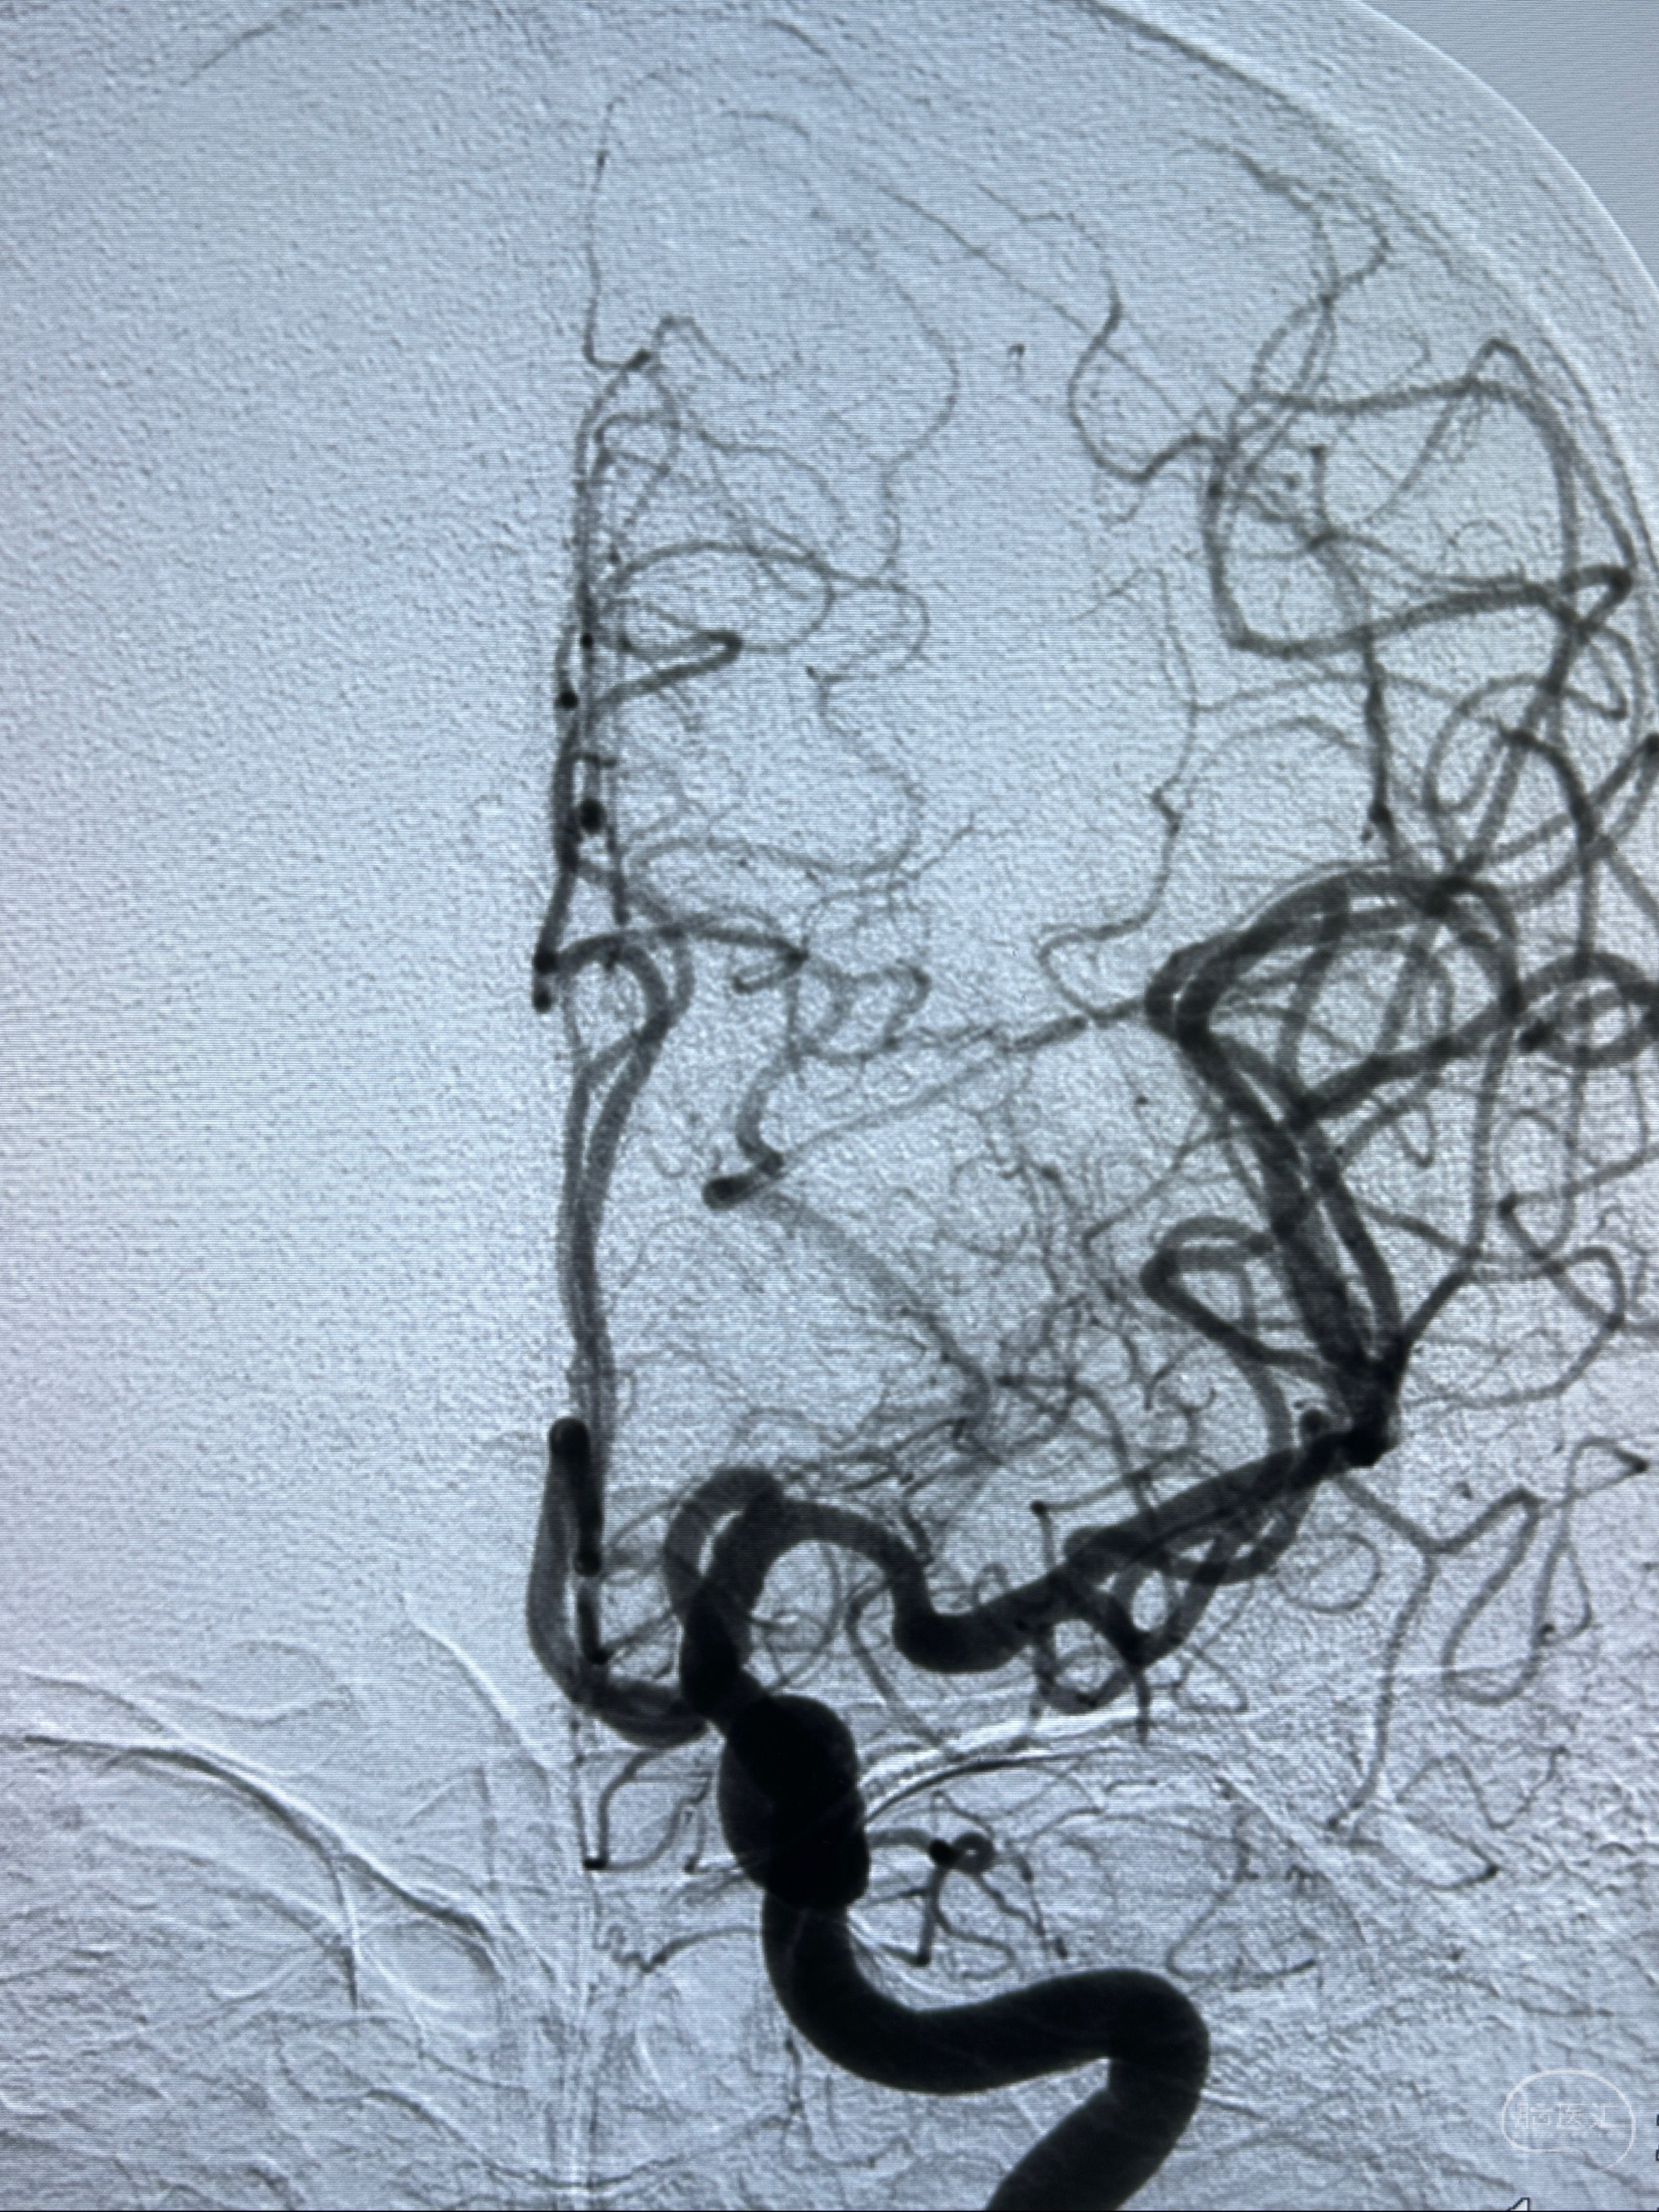

2023-12-04全麻下行支架辅助治疗

S-AB4-20mm

麻醉苏醒佳,遵嘱动作

术后即刻CT